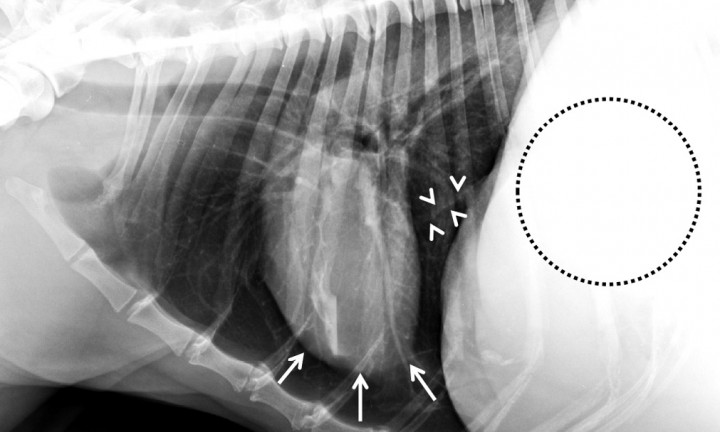

<p>Lebrel Afgano, hembra no castrada, 10 años. Radiografía lateral izquierda. Marcada ascitis, por fallo hepático por cirrosis. Marcada hipovolemia con imagen de microcardia. La silueta cardíaca ocupa 2 EIC, se encuentra elevada de su contacto esternal (flechas blancas), ocupado dicho espacio por tejido radiolúcido donde se identifican pequeños vasos pulmonares, por lo que no debe confundirse con neumotórax. Se trata de los lóbulos pulmonares. La vena cava caudal presenta un diámetro marcadamente reducido (cabezas de flecha) y los campos pulmonares se aprecian hiperlucentes (radiolúcidos) debido a un patrón pulmonar hipovascular. En el abdomen craneal incluido se observa un marcado aumento de la opacidad tejido blando, con pérdida del detalle de las serosas, debido a la presencia de ascitis (círculo punteado).</p>

Lebrel Afgano, hembra no castrada, 10 años. Radiografía lateral izquierda. Marcada ascitis, por fallo hepático por cirrosis. Marcada hipovolemia con imagen de microcardia. La silueta cardíaca ocupa 2 EIC, se encuentra elevada de su contacto esternal (flechas blancas), ocupado dicho espacio por tejido radiolúcido donde se identifican pequeños vasos pulmonares, por lo que no debe confundirse con neumotórax. Se trata de los lóbulos pulmonares. La vena cava caudal presenta un diámetro marcadamente reducido (cabezas de flecha) y los campos pulmonares se aprecian hiperlucentes (radiolúcidos) debido a un patrón pulmonar hipovascular. En el abdomen craneal incluido se observa un marcado aumento de la opacidad tejido blando, con pérdida del detalle de las serosas, debido a la presencia de ascitis (círculo punteado).